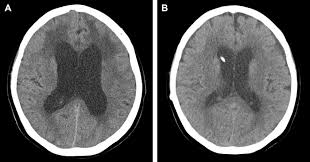

Brain Ct Scans Showing Normal Ventricles After Ventriculoperitoneal Download Scientific Diagram